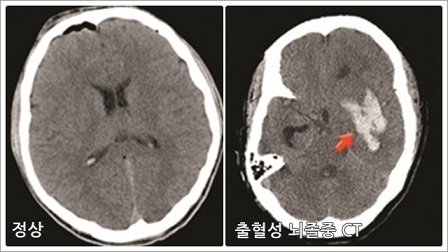

뇌 혈류랑 증가에 따른 <출혈성 뇌졸중>이 발병할 수 있습니다.

뇌경색 환자를 MRI로 확인한 결과 뇌출혈이 있다?

이사람에겐 아스피린은 '약' 이면서 '독'이 됩니다.

아스피린 복용시 심근경색 발병률 22%,

심혈관계 질환 사망률은 6%정도 감소시키는데 반해

부작용인 위장출혈 발생은 59%,

뇌출혈 위험은 33% 상승시킨다는

경희대 의대 분석결과도 있기때문이죠.